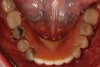

The periodontally involved mandibular

teeth were treatment planned for extractions followed by implant placement and delivery of an implant-supported removable prosthesis.

Fig 3